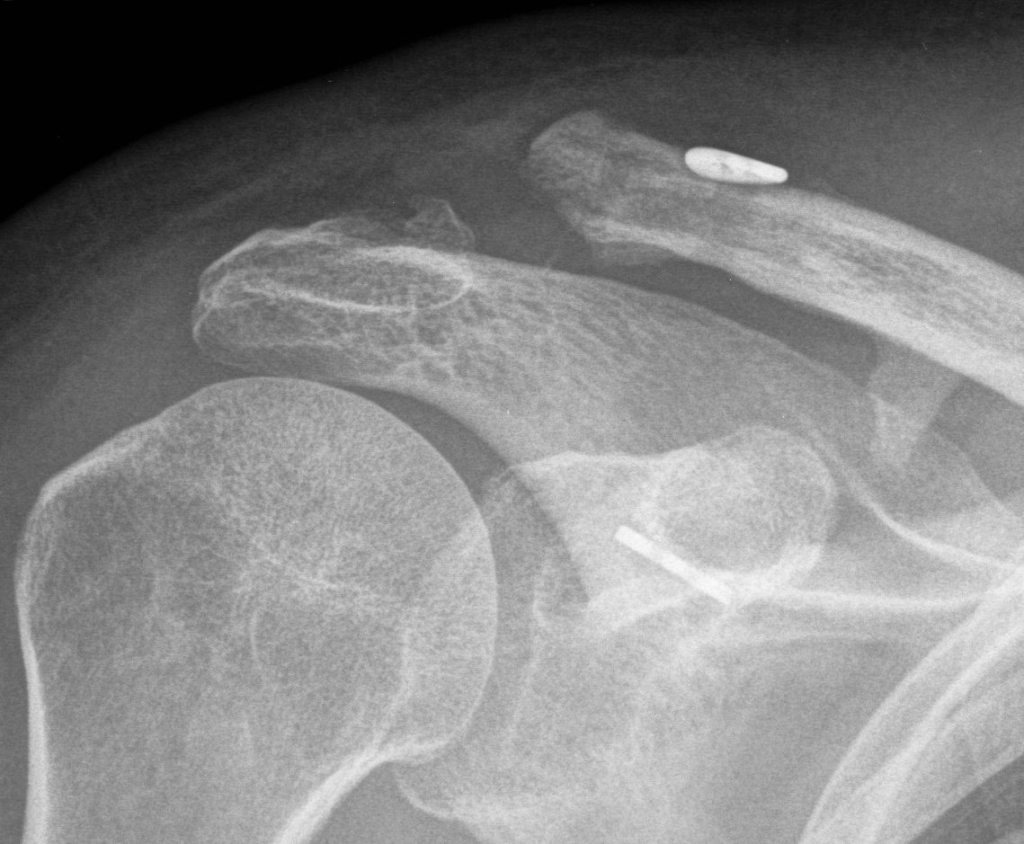

Dr Tim Dwyer is an orthopedic surgeon specializing in sports medicine and arthroscopy, performing surgery of the hip, knee and shoulder. Based at Women’s College and Mt Sinai Hospital, Dr Dwyer performs high volume ACL reconstruction, hip arthroscopy, rotator cuff repair, and operations for shoulder dislocation.